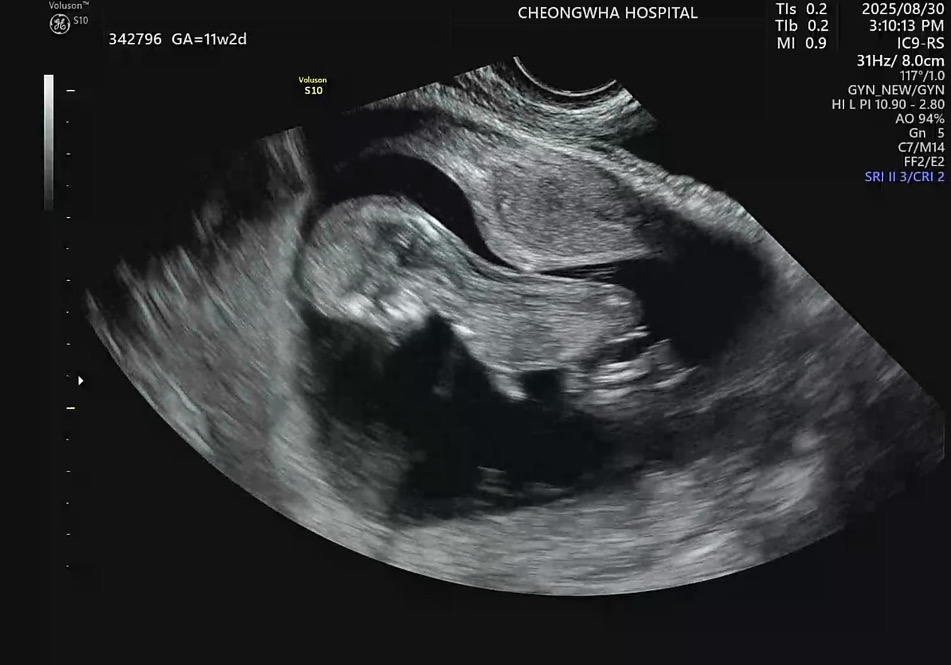

11주차도 각도법이 봐지려나요..! 엎드려있긴한데!!

엎드려도 각도법이 봐질까요..? ㅠ 넘 궁금해요..베이킹소다는 딸나오긴 했슴다..